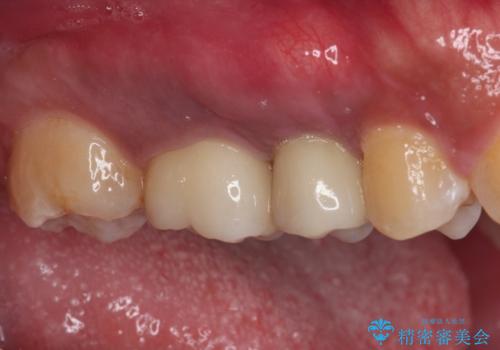

破折して抜歯が必要となった歯の後ろの歯は、根管治療が必要な状態であったので、根管治療を行い、矯正治療後にインプラント部の補綴治療と同時にセラミッククラウンを装着しました。